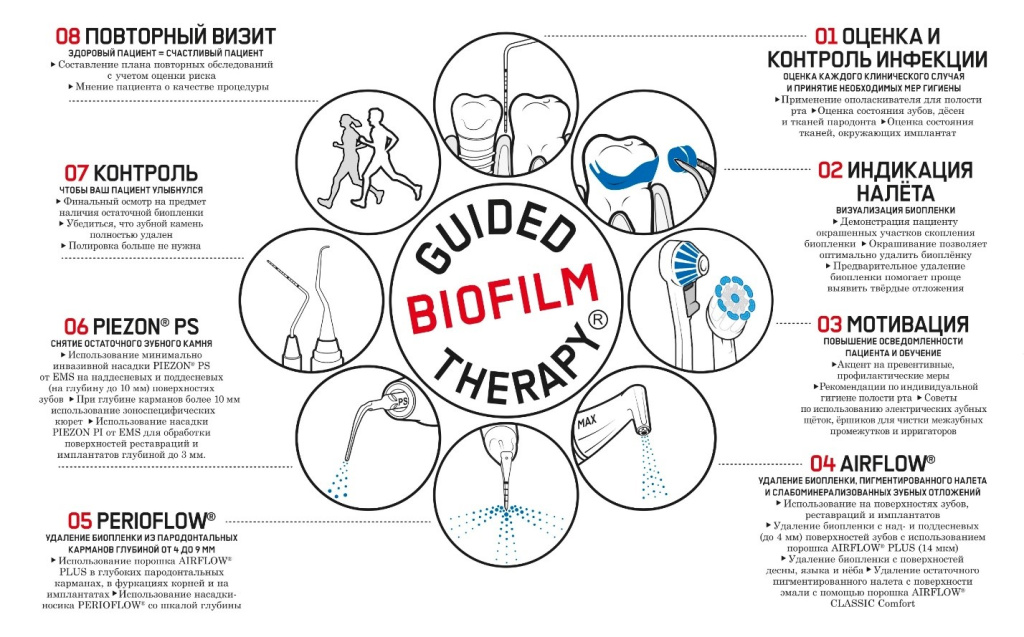

Guided Biofilm Therapy (GBT, EMS). дает возможность соответствовать вышеуказанным требованиям с учетом четко обозначенного протокола и соответствующих инструментов. Важно следовать данному систематическому протоколу, поскольку это позволяет облегчить врачу и пациенту проведение процедуры профессиональной гигиены полости рта.2 Цель данной статьи – ответить на часто задаваемые вопросы и тем самым способствовать эффективному лечению, щадящему для мягких и твердых тканей (рис. 1)..

Рис. 1. Guided Biofilm Therapy (GBT) благодаря четко сформулированному протоколу упрощает повседневную работу стоматолога

1-Й ЭТАП GBT: ОЦЕНКА И КОНТРОЛЬ ИНФЕКЦИИ

1-Й ЭТАП GBT: ИНДИКАЦИЯ ЗУБНОГО НАЛЕТА

ЗАЧЕМ?

Только индикация зубного налета позволяет полностью (95–100 %) устранить наддесневую биопленку.7 Этот факт также подтверждает исследование, проведенное Stiftung Warentest (независимая экспертная организация, осуществляющая потребительские испытания) относительно качества профессиональной чистки зубов (PTC – Professional tooth cleaning) в 10 стоматологических клиниках. Без применения индикации зубного налета удалось устранить только приблизительно 50 % биопленки. В частности, обнаружено недостаточное удаление в критических местах (в пришеечной области и в межзубных пространствах). Биопленка является причиной развития наиболее распространенных стоматологических заболеваний. Индикацию биопленки необходимо проводить для:

3-Й ЭТАП GBT: МОТИВАЦИЯ

4-Й и 5-Й ЭТАПЫ GBT: AIRFLOW®/PERIOFLOW®

6-Й ЭТАП GBT: PIEZON® PS

7-Й ЭТАП GBT: КОНТРОЛЬ

8-Й ЭТАП GBT: ПОВТОРНЫЙ ВИЗИТ